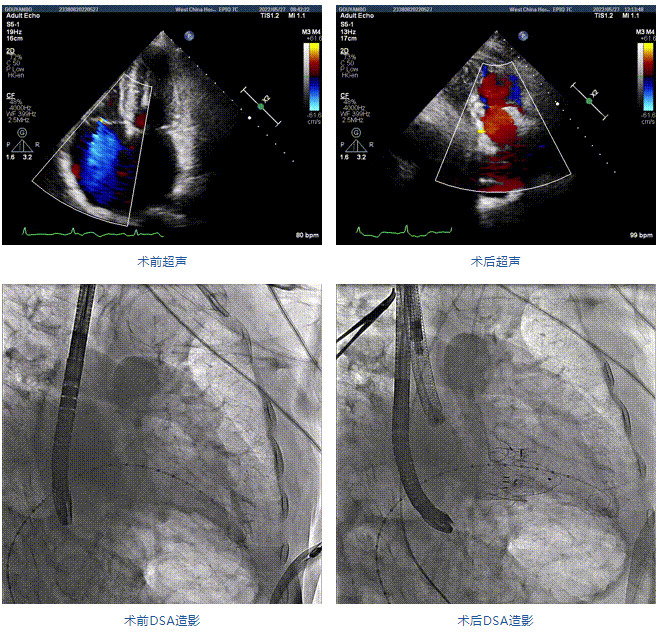

89歲男性。術(shù)前超聲報(bào)告顯示:雙房增大,左室壁肥厚,主、肺動(dòng)脈增寬,三尖瓣重度反流。

團(tuán)隊(duì)前期經(jīng)過(guò)多次討論,制定了周密的手術(shù)策略和預(yù)案。由于患者已是近九旬的超高齡老人,傳統(tǒng)外科開(kāi)胸手術(shù)風(fēng)險(xiǎn)極高,純介入經(jīng)血管三尖瓣替換能夠明顯減少創(chuàng)傷。術(shù)中陳茂及馮沅教授結(jié)合體表定位在造影指示下精準(zhǔn)穿刺右側(cè)頸靜脈并預(yù)置兩把血管縫合器。成功建立經(jīng)皮血管入路后在食道超聲和DSA的引導(dǎo)下順利完成人工瓣膜植入,術(shù)后超聲和造影顯示人工三尖瓣同軸性良好,瓣架固定牢靠,無(wú)反流和瓣周漏,平均跨瓣壓差降為1mmHg。術(shù)畢收緊預(yù)置的血管縫合器縫線完成止血,縫合效果滿(mǎn)意,在手術(shù)室即刻拔除氣管插管。